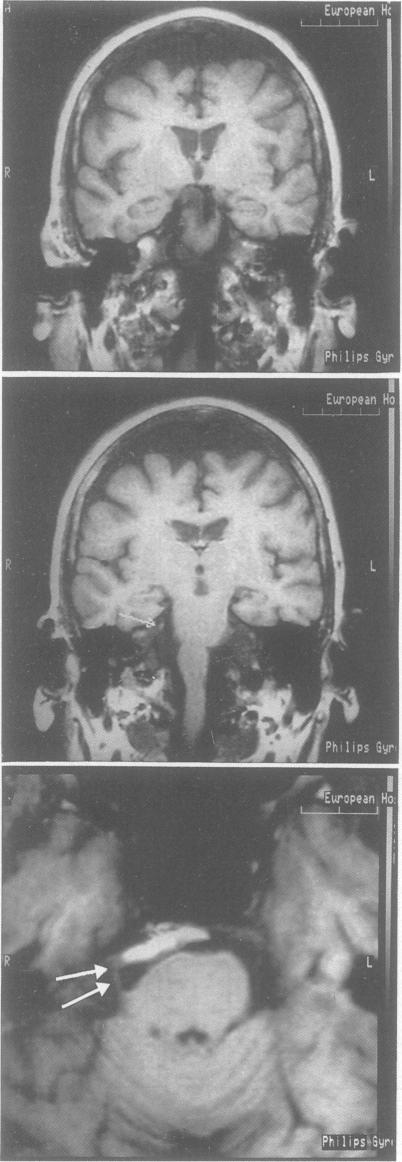

The trigeminal reflexes (corneal reflex, blink reflex, masseter inhibitory periods, jaw-jerk) and far field scalp potentials (nerve, root, brainstem, subcortical) evoked by percutaneous infraorbital stimulation were recorded in 30 patients with "idiopathic" trigeminal neuralgia (ITN) and 20 with "symptomatic" trigeminal pain (STP): seven postherpetic neuralgia, five multiple sclerosis, four tumour, two vascular malformation, one Tolosa-Hunt syndrome, and one traumatic fracture. All the patients with STP and two of those with ITN had trigeminal reflex abnormalities; 80% of patients with STP and 30% of those with ITN had evoked potential abnormalities. The results indicate that 1) trigeminal reflexes and evoked potentials are both useful in the examination of patients with trigeminal pain, and in cases secondary to specific pathologies provide 100% sensitivity; 2) in "symptomatic" and "idiopathic" paroxysmal pain the primary lesion affects the afferent fibres in the proximal portion of the root or the intrinsic portion in the pons; 3) primary sensory neurons of the A-beta fibre group are involved in both paroxysmal and constant pain, but in the latter the damage is far more severe.

对30例“特发性”三叉神经痛(ITN)患者和20例“症状性”三叉神经痛(STP)患者记录了经皮眶下刺激诱发的三叉神经反射(角膜反射、瞬目反射、咬肌抑制期、下颌反射)和远场头皮电位(神经、神经根、脑干、皮质下):7例为带状疱疹后神经痛,5例为多发性硬化,4例为肿瘤,2例为血管畸形,1例为托洛萨-亨特综合征,1例为外伤性骨折。所有STP患者及2例ITN患者存在三叉神经反射异常;80%的STP患者及30%的ITN患者存在诱发电位异常。结果表明:1)三叉神经反射和诱发电位在三叉神经痛患者检查中均有用,在继发于特定病变的病例中敏感性达100%;2)在“症状性”和“特发性”阵发性疼痛中,原发损害影响神经根近端部分的传入纤维或脑桥内的固有部分;3)A-β纤维组的初级感觉神经元参与阵发性和持续性疼痛,但在持续性疼痛中损害更为严重。